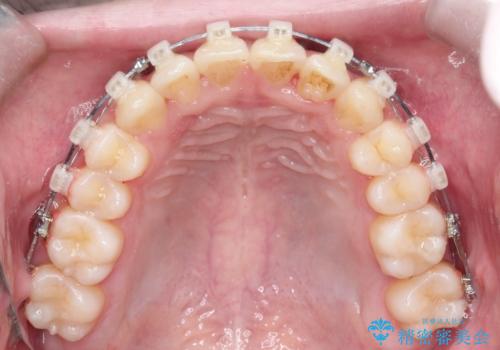

【クリア装置】前歯の凸凹を綺麗にしたい

- 矯正装置

- クリア装置

- 前歯の凸凹を主訴に来院されました。

マウスピース矯正も適応でしたが、ワイヤー矯正を希望され治療を行なっております